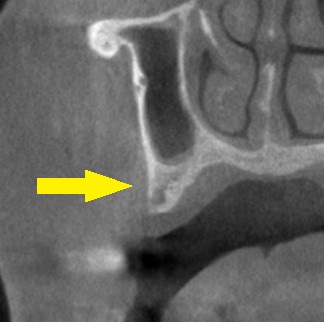

CTを撮影してみると、第二小臼歯部は骨幅が狭く(下の写真上段左)、第一大臼歯部は骨が薄く、高さが不足していました(下の写真上段右)。

そこで、第二小臼歯部には、側方に人工骨を補填して、骨幅を増やす骨造成を行い、通常サイズのインプラントを埋入。